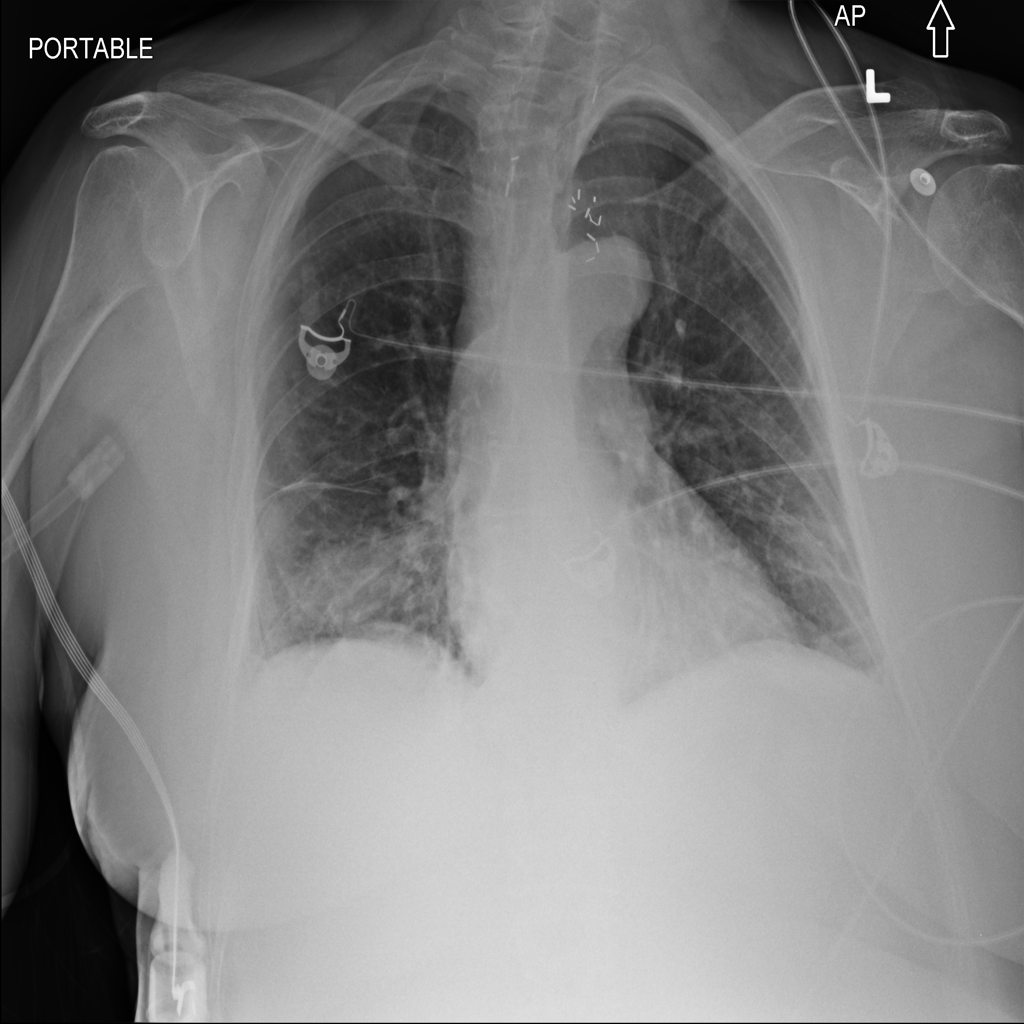

PAT-4639 · IMG-013Pneumothorax

PAT-4639 · IMG-013

AP